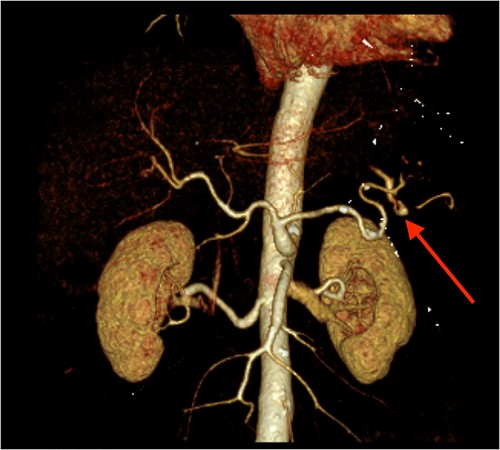

Triple-phase computed tomography (CT) of the abdomen and pelvis revealed a sizeable acute haematoma in the left upper abdomen, below the gastric fundus and body, alongside the pancreatic tail and splenic hilum, extending amongst the proximal small bowel mesentery and into the left subphrenic space. The origin of the haemorrhage appeared to arise from the left upper quadrant. There was a pseudoaneurysm in close proximity to the pancreatic tail and splenic hilum, apparently arising from the adjacent distal splenic artery. CT scan did show local contrast extravasation into the haematoma, as mentioned above (Figs 1–3).

CT angiography of the abdomen with 3D reconstruction. Ruptured SAP.